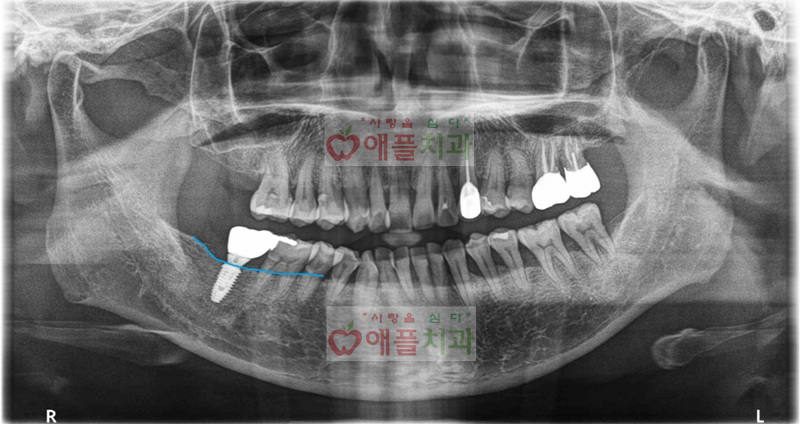

<골이식 + 임플란트 치료 완료>

골이식 + 임플란트 수술을 잘 마무리되었으며, 현재까지 잘사용하고 계십니다.

애플치과에서는 3~4개월 주기마다 recall check를 하면서 임플란트 케어를 해드립니다.

임플란트는 수술을 잘하는것도 중요하며, 자연치아처럼 지속적인 관리도 굉장히 중요하다고 생각합니다.